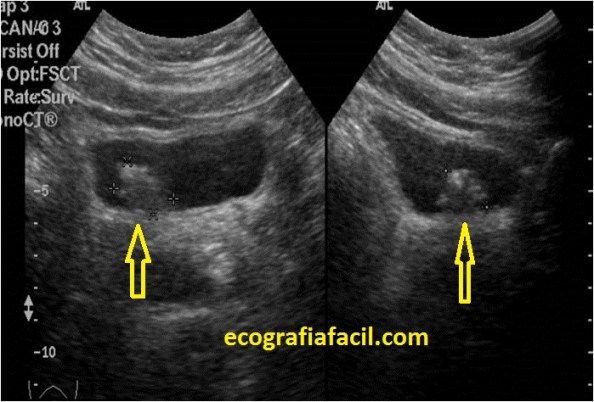

Divertículo Vesical:

El Divertículo Vesical se verá como una imagen anecoica al igual que la Vejiga exofítica a la pared de la vejiga, pero unida, como si de un desfiladero se tratase, pueden ser varios o uno solo…En su interior pueden contener patología.

En la imagen los ves señalados con flecha amarilla.